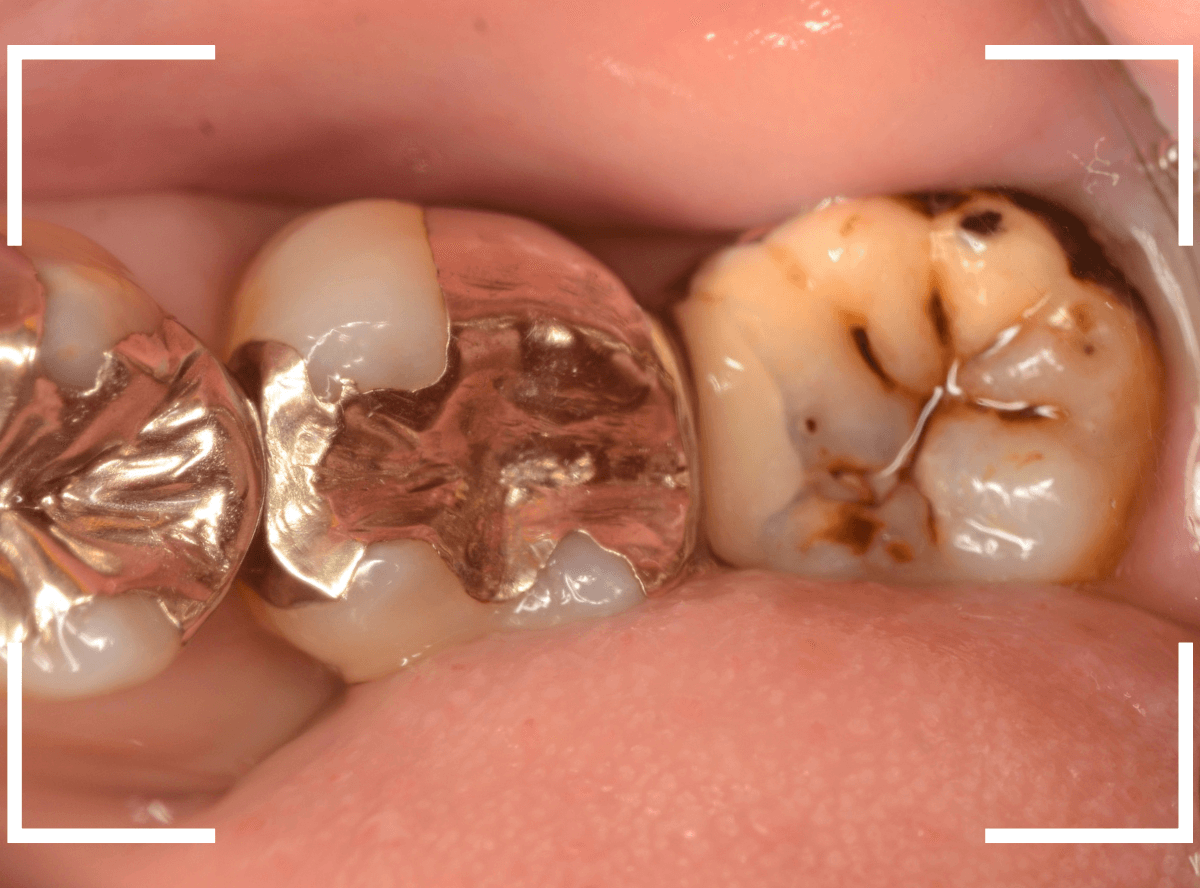

今回は、「下の奥歯が痛む」という訴えで来院された患者さんのケースです。

お口の中を確認すると、一番奥(右側)のおやしらずが虫歯のようです。

側面から確認します。

手前の歯の根元がボロボロなのも確認できます。